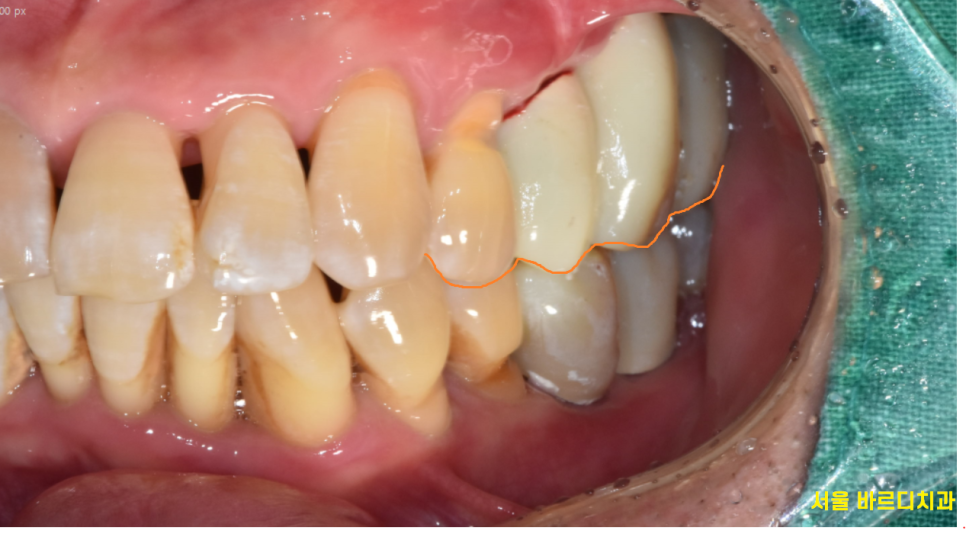

일반적으로 윗니가 아랫니를 덮게 되는 형태인데

이런 형태가 되었을 때

저작

씹는 운동을 시행할 때

볼을 밀어내기 때문에

볼 씹힘 발생하지 않습니다.